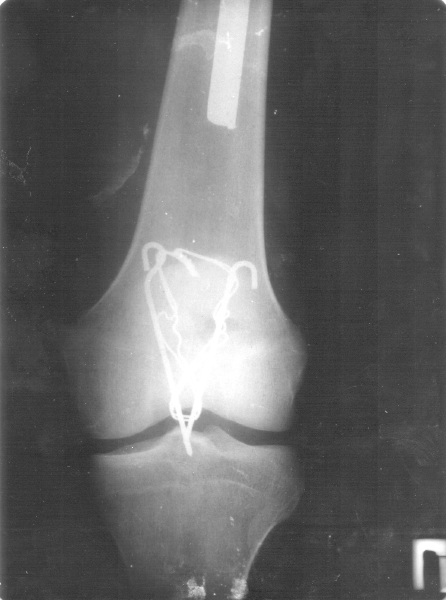

всё зависит от того, как сращиваться будет, каждый месяц со фотографиями появляюсь, они смотрят. вообще пол года примерно сращение идёт, но это всё индивидуально,

сегодня только два мес. как кости свели друг к другу. вобще "бывалые" говорят что долгая история, типо пару лет минимум будещь так мучиться, х.з. откуда такие прогнозы конкректно ко мне. вообще в больнице столько нытиков, послушаешь так писец, я никогда не слушал, настрой всегда только на позитив, как бы хреного и устрашающе не было, даже во сне брёл - "всё будет за и бись!" Но и позавидовать терпеливости некоторых тоже можно было. Я лежал в таком отделении, где были люди все в железе, смотреть дурно, мы с тобой ещё "счастливые" люди по сравнению. кстати мысли вроде как материализуются, так что только только не падай духом, товарищ по несчастью. И на нашей улице камаз с водкой перевернётся! (с).